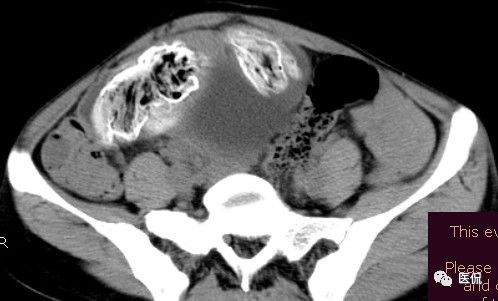

腹腔内残留的纱布在人体内引起渗出或液化坏死并纤维包裹形成异物性脓肿(纱布瘤)。纱布瘤的影像特点:圆形或卵圆形肿块,较大,有完整包膜,薄壁,较少的情况下为厚壁,边界较完整,增强后薄膜可以持续强化。不同时期的纱布瘤可以有不同表现:早期(10个月或半年内)多表现为蜂窝状;2~5年内一般表现为囊性飘带状;10~20年之后则为实性软组织密度,包膜钙化呈钙化网状结构。手术过程中残留在人体内的医用纱布所形成的肿瘤样病变。

手术所见:腹腔内无腹水,肿块位于右上腹,约15x10x8cm大小 ,周围网膜包裹粘连,向胆囊三角处延续,呈囊性,与周围结构无明显浸润,仔细分离粘连,逐步游离暴露肿块,见肿块与右肾及结肠、十二指肠无明显关系,初步确定为肿大的胆囊,继续向肝门部游离,见肿块与胃窦粘连,因分离困难,决定切开肿块。穿刺肿块有黄色脓液抽出,考虑胆囊脓肿,切开囊壁,吸出大量黄色混浊脓液约1200ml,探查囊腔,见粘膜层为胆囊粘膜,腔内有一异物残留,经证实为医用盐水纱布,取出纱布约15x15cm大小,封存。继续游离胆囊至完整切除,检查囊壁无明显占位病变。

病理诊断:胆囊异物残留,胆囊化脓性炎、胆囊脓肿。

腹腔内遗留纱布团的影像学表现,以B超较具特征性,其主要表现为:腹腔或盆腔内特殊率减的黑色包块,后方伴有扇形衰减的声影,上窄下宽,好似一“黑色大布”,早期包块内含有不规则光团或光点,随时间延长有缩小或消失,为纱布团内气体。CT的优势在于早期常表现为软组织密度的肿块,其内可见多少不等的气泡,随时间的延长气泡逐渐被吸收减少至消失,增强扫描可见包膜不同程度强化而内容物无强化。熟悉其影像学表现,可在术前作出明确诊断。